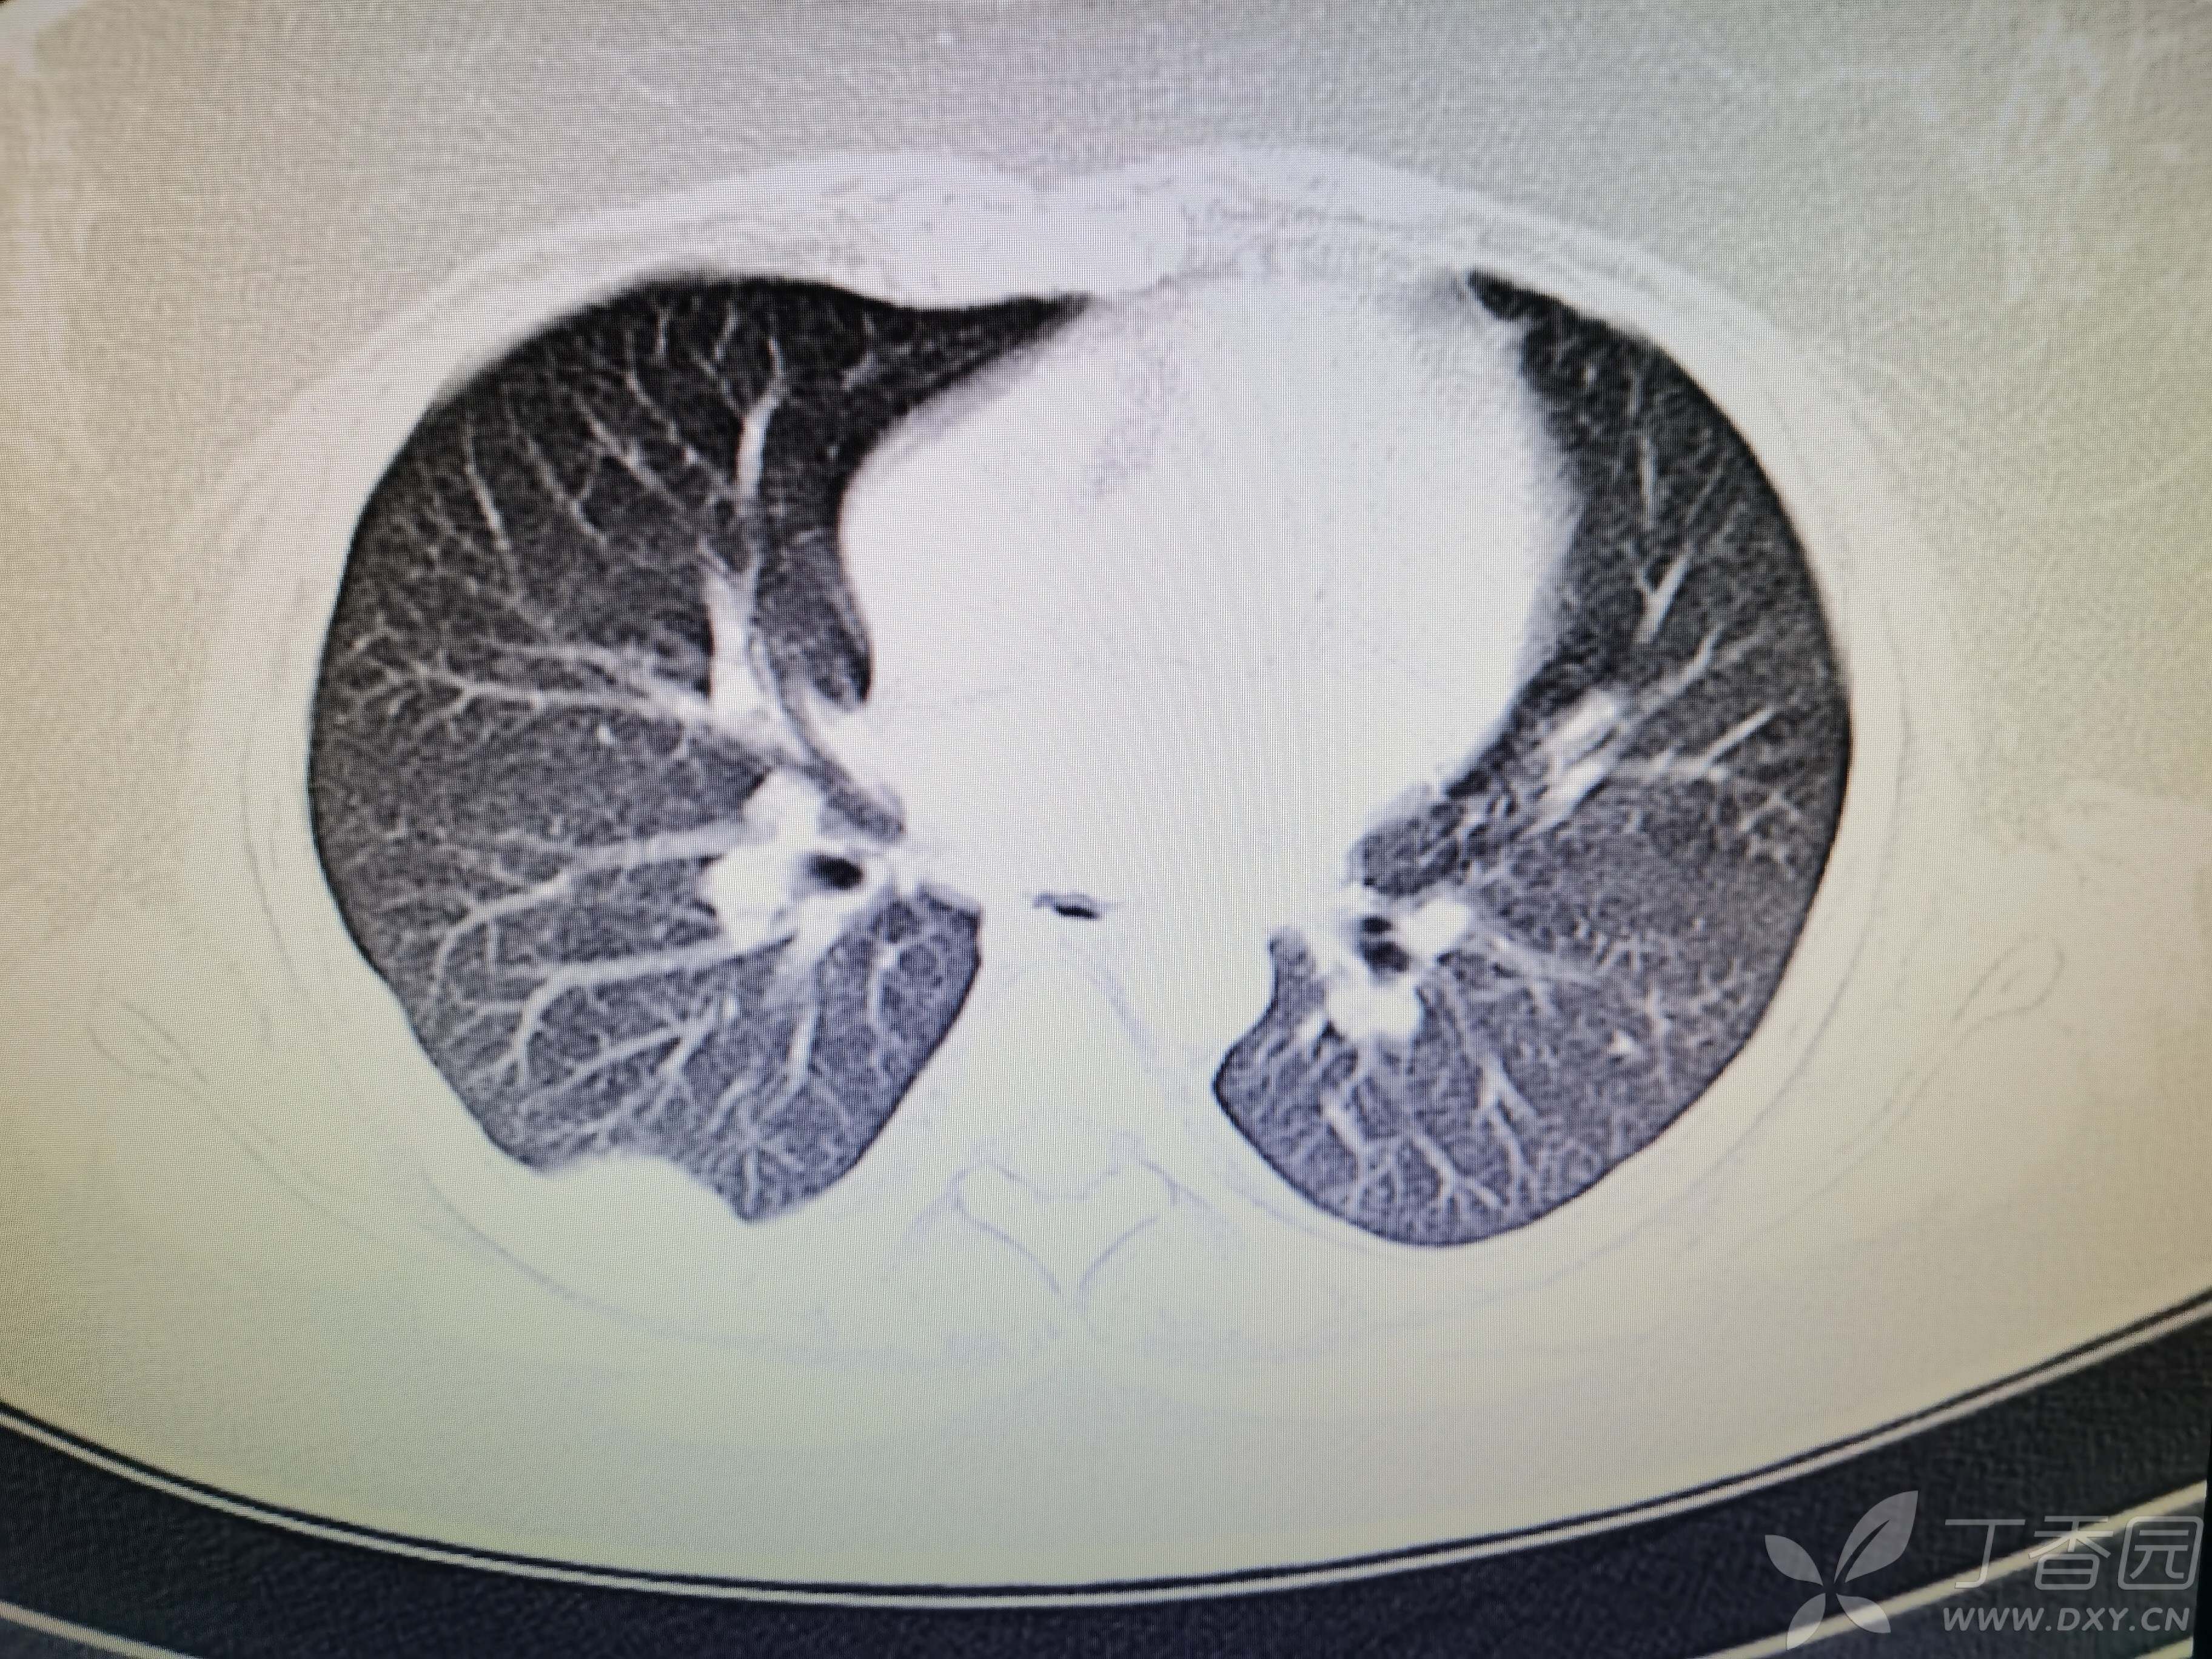

基本信息:女,三十几岁,印度人。。

胸部CT:

如题:猜肺部病灶病理。。